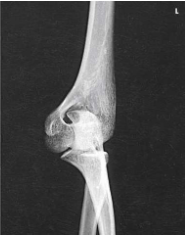

AP elbow

What projection, position, and anatomy is this?